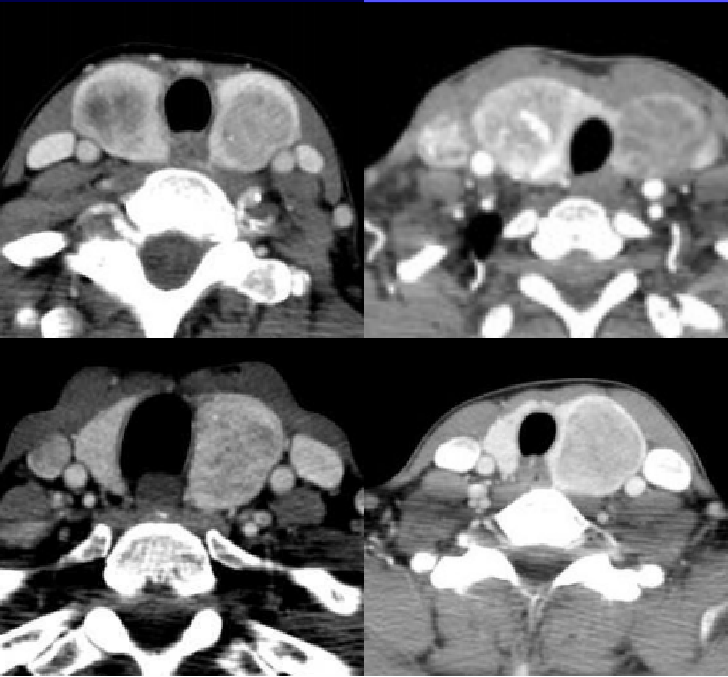

超声 CT平扫

CT平扫 CT增强

CT表现:甲状腺右侧椭圆形低密度影,平扫低密度,增强动脉期轻度磨玻璃样强化,静脉期强化程度低于周围甲状腺实质,病灶范围较平扫缩小,边界变模糊。结合超声,定性恶性,倾向甲状腺髓样癌。

MTC超声表现:多位于甲状腺中上极,这是因为滤泡旁C细胞主要位于中上极;散发性者多为单发,遗传性者多为双侧多发;结节相对较大,多具有规则的边缘,更易呈现为卵圆形,纵横比多<1,呈“躺鸡蛋”样;钙化发生率相对较低,且粗钙化发生率较高,较PTC的钙化灶更致密、更粗糙;CDFI多为高血供;发生淋巴结转移的几率高于PTC,转移淋巴结的回声与原发灶接近,且两者钙化表现一致,呈“子母瘤”样改变。值得注意的是,部分MTC无显著恶性征象:形态规则,边缘光整,边界清晰,无钙化,容易误诊。还应注意的是,部分MTC的超声表现与甲状腺腺瘤类似,都表现为单发性类圆形低回声结节;但两者存在不同之处:① 髓样癌多位于腺体中上部,钙化发生率较高:② 髓样癌多无包膜,而腺瘤则有完整包膜;③ 髓样癌边缘的声晕不完整、厚薄不一,而腺瘤的声晕则完整、厚度均一;④ 髓样癌内部及周边血流丰富、紊乱,而腺瘤则多为环状血流,血管走行规则。CT表现为甲状腺内形态不规则、边缘不清肿物,可见不均匀强化伴内部不规则低密度区,部分可见点状或圆形钙化,增强扫描多明显强化。淋巴结转移多见,表现为与原发肿瘤一致的不均匀强化背景下低密度区。临床工作中,出现此类表现的甲状腺肿物患者,如降钙素显著升高,应考虑MTC的可能,确诊需结合病理及免疫组化,此外应全面检查除外其他部位的远处转移。微小MTC的影像学表现与非微小MTC有很多相似之处,如实性、低回声、钙化、无声晕、血供丰富等,但也具有一定的特别征象,如形态不规则等,后者极易与微小PTC混淆。与超声比较,CT在微小MTC显示、判断上不及超声检查。

CT四大主征:1.低强化、2.钙化、3.形态规则、4.甲状腺中上极。